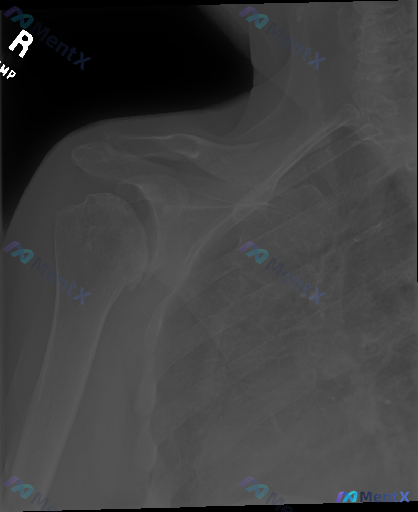

整理了一份有意思的影像资料: - 影像类型:右肩部X光正位 - 核心所见:骨骼完整性良好,肱骨近端、肩胛骨、锁骨远端骨皮质连续;盂肱关节、肩锁关节对合正常;骨小梁清晰,无溶骨/硬化/明显钙化;无骨赘形成,软组织影无明显肿胀。 - 影像总结:未见明显骨性病变。 但临床背景是「存在异常/症状」。 想先问...

整理了一份右肩X光的影像分析资料,觉得这个「同影异病」的点很值得拿出来讨论。 先放影像客观描述: - 骨皮质:肱骨近端、肩胛带、锁骨远端连续,未见明确骨折线 - 关节:盂肱关节间隙、对合关系正常,无脱位半脱位,退行性变不显著 - 软组织:无明显肿胀 - 重点异常:肱骨大结节上方、冈上肌腱附着区域可见...